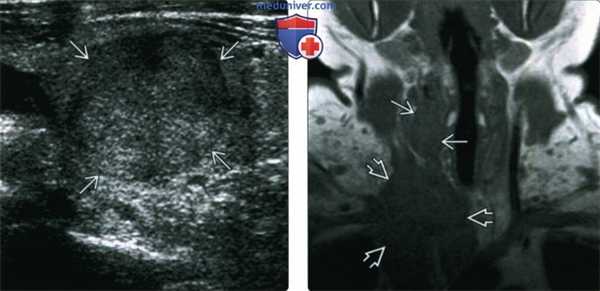

(Слева) УЗИ в продольной проекции. В щитовидной железе определяется солидное образование с четкими контурами и гипоэхогенным гало. Какие-то специфические признаки, которые бы позволили отличить опухоль от аденомы или дифференцированной карциномы, отсутствуют.

(Справа) При МРТ Т1ВИ в коронарной проекции у пациента, которому выполнена тиреоидэктомия по поводу спорадического медуллярного рака щитовидной железы, справа, в ложе щитовидной железы определяются признаки рецидива. Крупная инфильтрирующая опухоль спускается в верхнее средостение, окружает сосуды и сдавливает правую яремную вену. Образование является рецидивом медуллярного рака.

4. УЗИ при медуллярном раке щитовидной железы:

• Серошкальное УЗИ:

о Гипоэхогенное образование щитовидной железы с неправильными контурами

• Цветовая допплерография:

о Гиперваскуляризация с неравномерным распределением сосудов